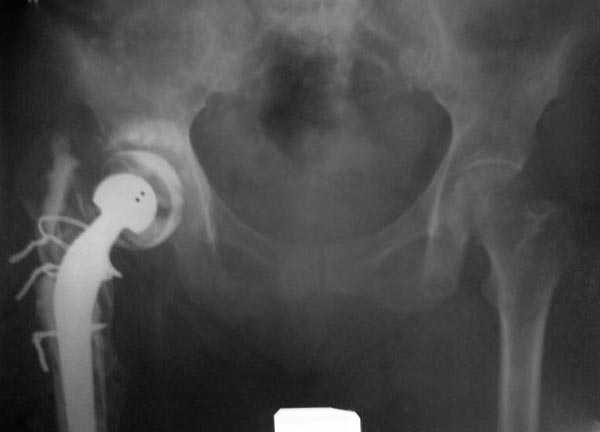

Если снимок справа по хронологии последний, то в тазобедренном сустава наступил анкилоз. Это хороший плюс костной ткани для постановки чашки эндопротеза, но отсутствие сохранения биомеханической оси бедренной кости ставит под вопрос благоприятный вариант усановки ножки эндопротеза.... Учитывая выполненную остеотомию, не считаю выполнение скелетного вытяжения лишенным смысла, для восстановления оси конечности с последующим, возможно, индивидуальным эндопротезированием.

Очень признателен Вам за ответ, но позвольте мне не согласиться с Вами. Я бы пока не делал вывод о анкилозировании тазобедренного сустава. На рентгеновских снимках, да и по данным компьютерной томографии (а этот метод один из самых современных и информативных), хорошо прослеживается постоянной ширины щель между головкой бедренной кости и вертлужной впадины. Кроме того, несложно увидеть разницу "шеечно-диафизарного угла" до и после выполнения тракции в аппарате. Хотя, Алексей, даже если я и прав, это не сильно облегчает нашу задачу.